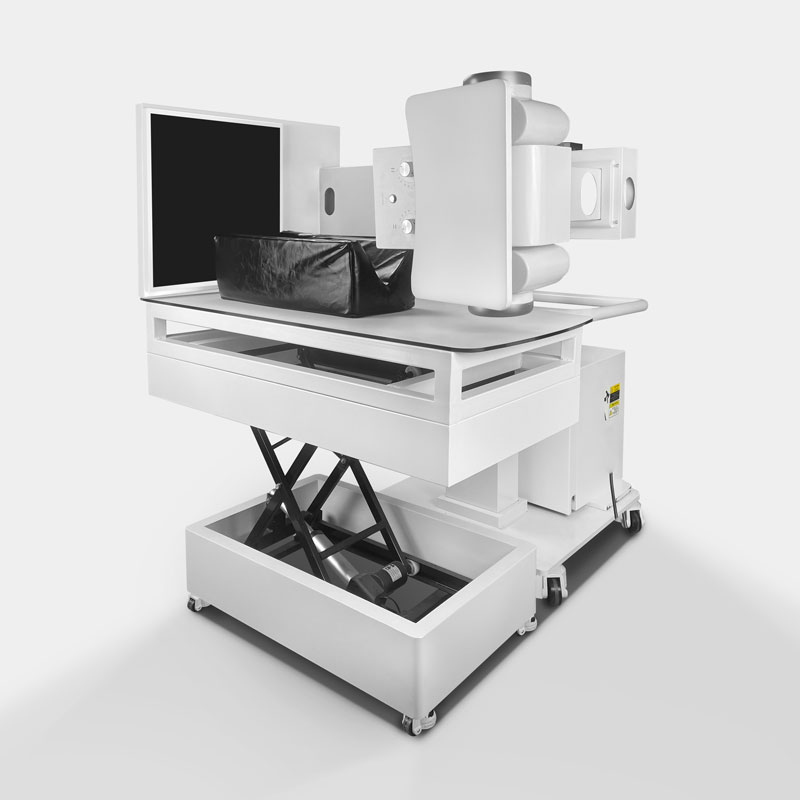

Организация рабочего пространства: стенды для рентгеновских снимков